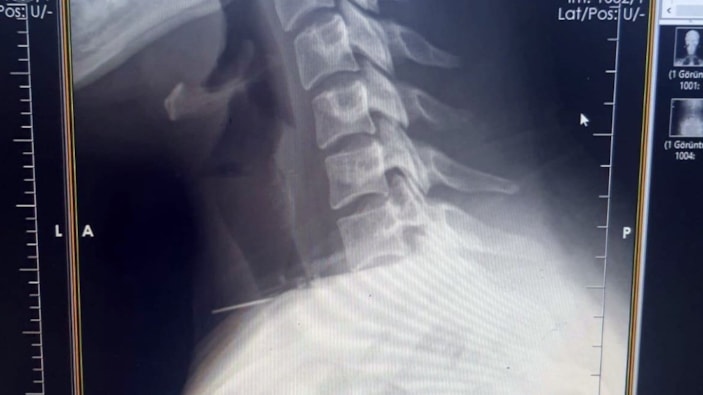

Boğazına dikiş iğnesi saplanması sonrası hastaneye başvuran kadına burada yapılan incelemelerde, 3 santimetrelik iğnenin boğaz bölgesinin derinliklerine doğru ilerlediği tespit edildi.

Radyolojik incelemeler ve klinik değerlendirmeler sonucunda, 3 santimetrelik iğnenin boğaz bölgesinin derinliklerine doğru ilerlediği belirlendi.